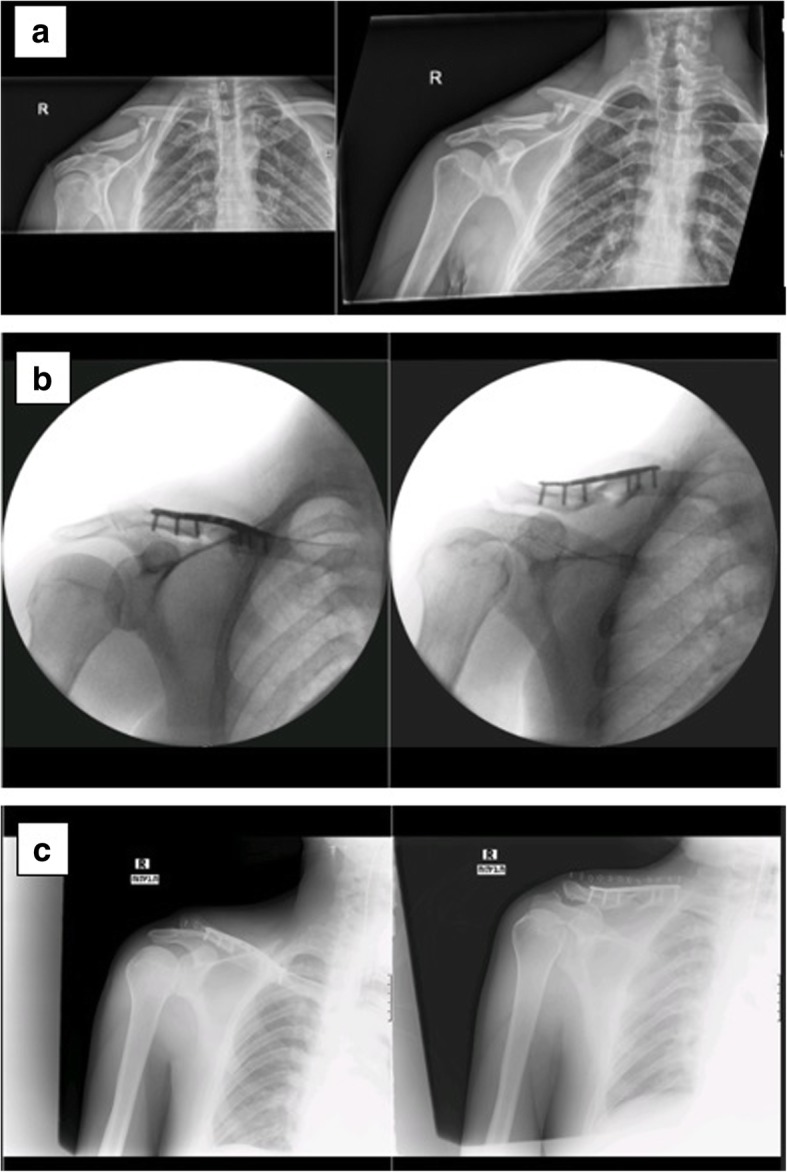

Fig. 1.

a X-ray: displaced comminuted right midshaft clavicle fracture; b intraoperative imaging; c postoperative X-ray with reduction and bridging osteosynthesis with an anatomical contoured locked plate

Fig. 2.

Postoperative 2-week follow-up X-ray